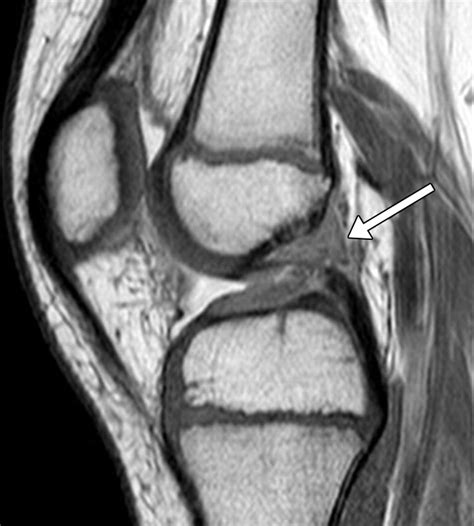

Ligaments

The knee has several important ligaments, including the anterior cruciate ligament (ACL), posterior cruciate ligament (PCL), medial collateral ligament (MCL), and lateral collateral ligament (LCL). The MRI can show tears or strains in these ligaments, which are often the result of sports injuries.

• normal knee mri sagittal